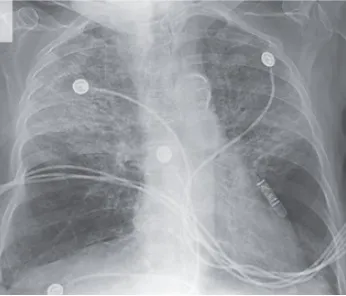

¡Atención al uso prolongado de Nitrofurantoína en ITU recurrente!

¡Atención al uso prolongado de Nitrofurantoína en ITU recurrente!